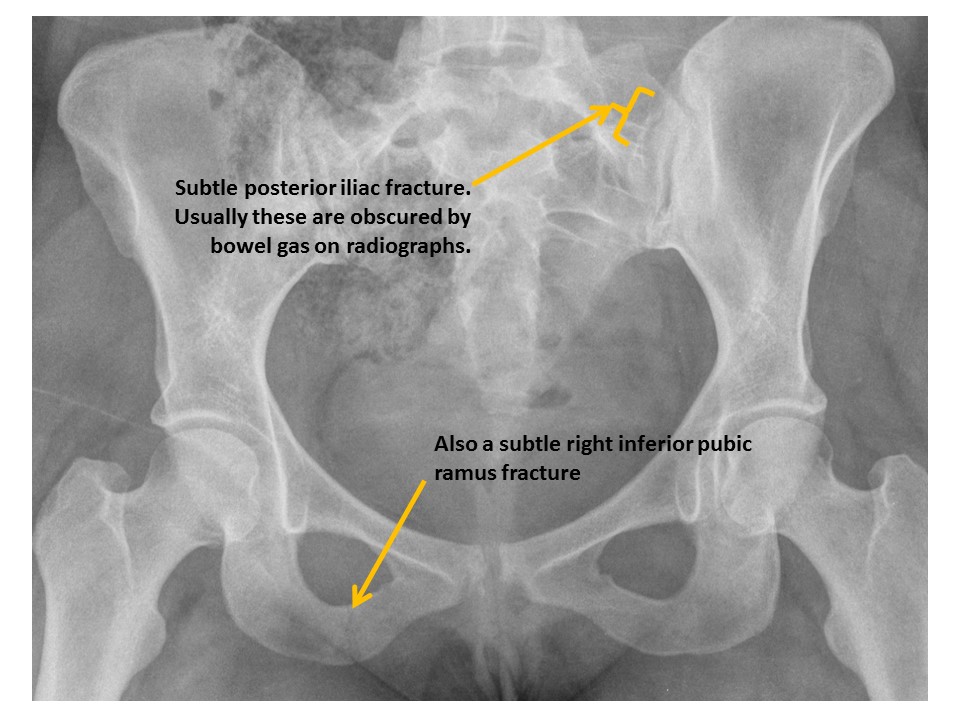

There is a pubic ramus fracture. [Yes/No]

ILIAC BONES

Iliac wing fractures are present.

[Yes/No]

Posterior iliac bone fractures are present. [Yes/No]